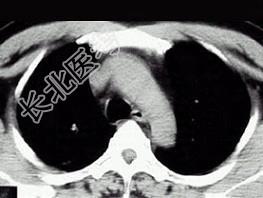

- 单项选择题21岁,近2个月来咳嗽, 痰中带血丝,午后手心足底发热, 盗汗、心悸,胸部CT见图, 最可能的诊断是 ( )

A、右上肺癌性空洞形成

B、继发性肺结核空洞形成

C、右肺脓肿

D、右上肺炎

E、肺囊肿